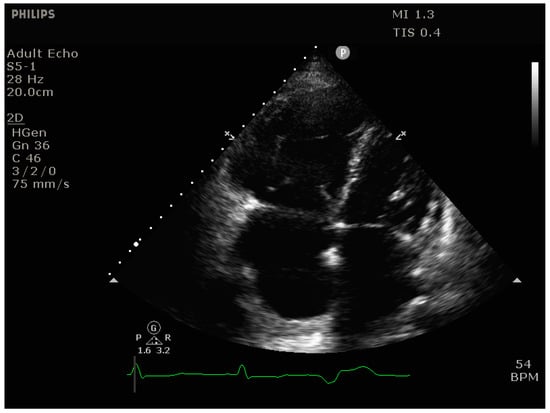

4.2.2. Echocardiography

- Signs of RV dilation: D-shaping, increased RV:LV ratio, tricuspid regurgitation

- Signs of impaired RV systolic function: reduced tricuspid annular plane systolic excursion (TAPSE)

- Signs of elevated RV preload (plethoric inferior vena cava [IVC])